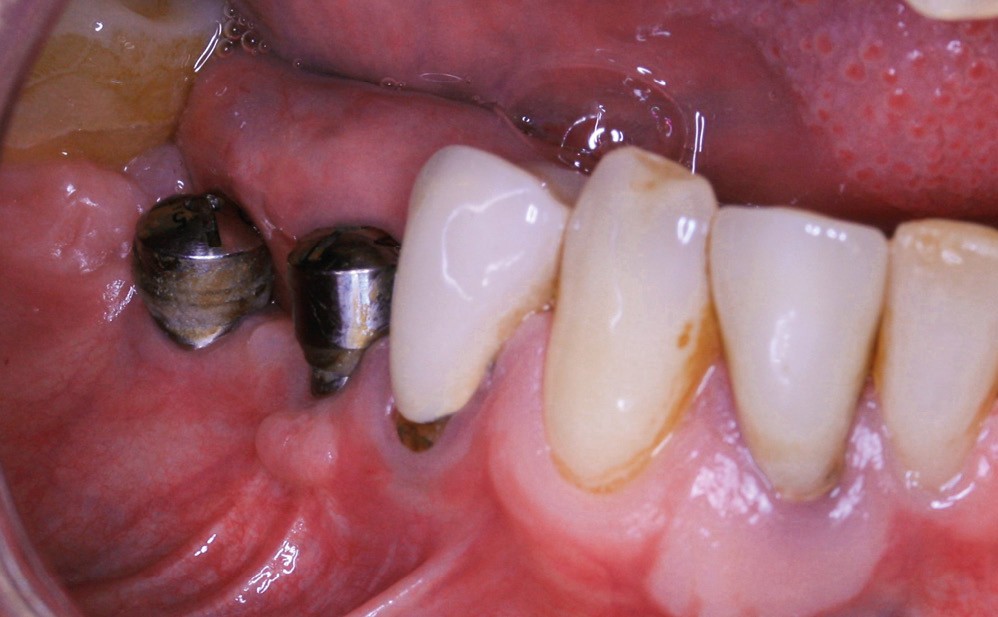

La greffe épithélio-conjonctive (GEC) [7, 8] consiste au remplacement du tissu parodontal existant par un greffon épithélio-conjonctif dont l’indication principale est l’augmentation en hauteur et en épaisseur du tissu kératinisé (fig. 2). Elle peut aussi être utilisée dans le recouvrement radiculaire (avec des résultats en termes de recouvrement inférieurs à ceux des techniques de greffe de conjonctif enfouie), l’aménagement des crêtes édentées, l’aménagement péri-implantaires [9, 10] (fig. 3), ou en association avec un traitement ortho-parodontal [11]. Le principal défaut de cette technique est son aspect inesthétique ; elle sera donc réservée à des zones non visibles comme les incisives mandibulaires ou les zones postérieures.